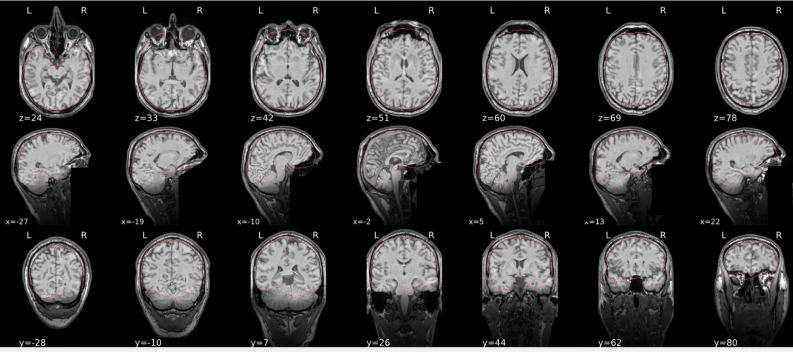

Example of a bad subject

- There are skull stripping errors, such as portions of the brain missing, or too much of the skull retained

- NOTE: check all the images (slices) in the report. If only one image (slice) looks problematic, it is possible that the subject is okay and it is just a visual issue in that particular screenshot

Summary

| Good | Bad |

|---|---|

| The brain is fully inside the red line | Structures like the cranium or the eyes are inside the red line |

| No important brain structures are outside of the red line red line follows the natural outline of the brain | Important brain structures are missing inside of the red line |

-> if only one slice is problematic, it could be an issue related to the visual depiction of the data instead of an issue related to the test subject